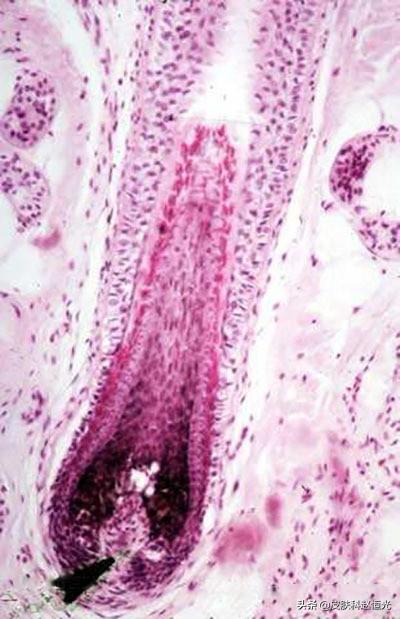

药物通过口服、注射等途径进入机体后,损伤了毛发的生长环境或改变了毛发组织结构,从而引起了毛发脱失称为药源性脱发。其特点是,以毛母质细胞直接受损为主,进展迅速。